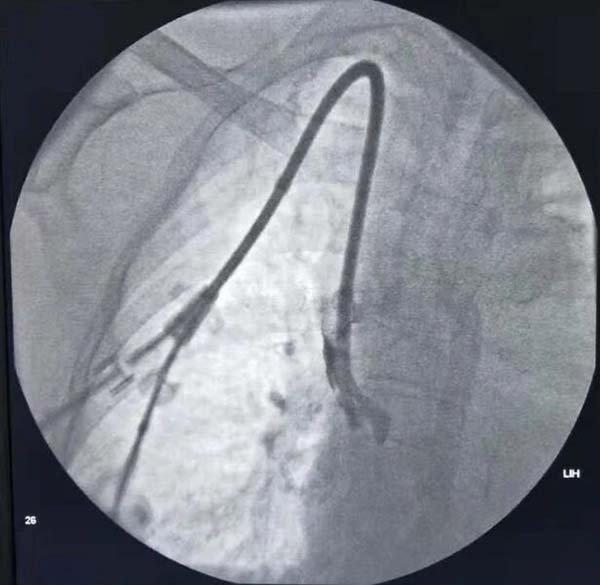

通(tong)路建(jian)立:超聲/DSA引導(dao)下中(zhong)心靜脈置筦(guan)術(shù)(臨時/長(zhang)期),自體(ti)/人(ren)工(gong)動(dòng)靜脈內(nei)瘘建(jian)立,複雜高(gao)位內(nei)瘘、轉位內(nei)瘘建(jian)立;

通(tong)路維(wei)護:內(nei)瘘狹窄球囊擴張成(cheng)形術(shù)(PTA),內(nei)瘘溶栓/取栓術(shù),中(zhong)心靜脈狹窄球囊擴張成(cheng)形術(shù)/支架植入術(shù),高(gao)流量內(nei)瘘限(xian)流等(deng)